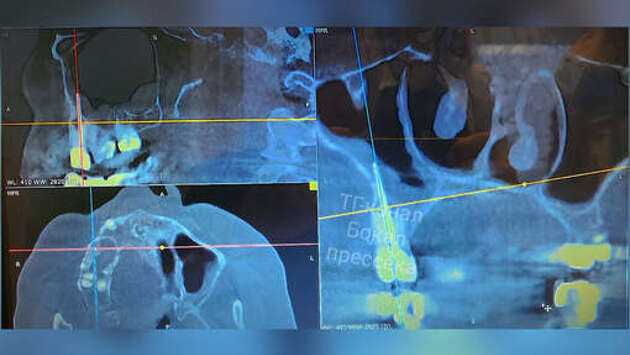

Житель Нижнего Новгорода долгое время мучился болями в носу и в верхней челюсти, причиной такого состояния стал отломок стоматологического инструмента, забытый врачом во время проведения манипуляций. Об этом сообщил главный редактор местного издания "Стационар-пресс" Алексей Никонов в личном Telegram-канале. В итоге нижегородец обратился с жалобами в отделение челюстно-лицевой хирургии Нижегородской областной клинической больницы им. Н. А. Семашко. Он рассказал, что у него подозревали гайморит, но назначенная терапия облегчения не приносила. Хирурги медучреждения направили мужчину на дополнительное обследование. Во время КТ вскрылась истинная причина проблемы - боль причинял забытый отломок стоматологического инструмента. После этого часть инструмента удалили вместе с зубом, в котором он располагался. До этого в Омске пенсионерка через суд добилась компенсации за удаление здорового зуба.